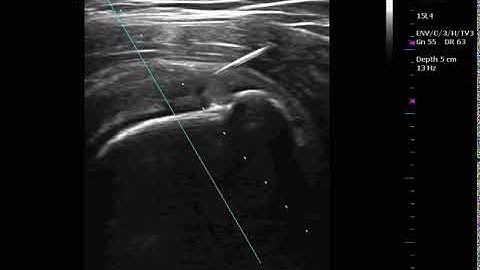

Partial thickness rotator cuff tear, injection of stem cells into tendon